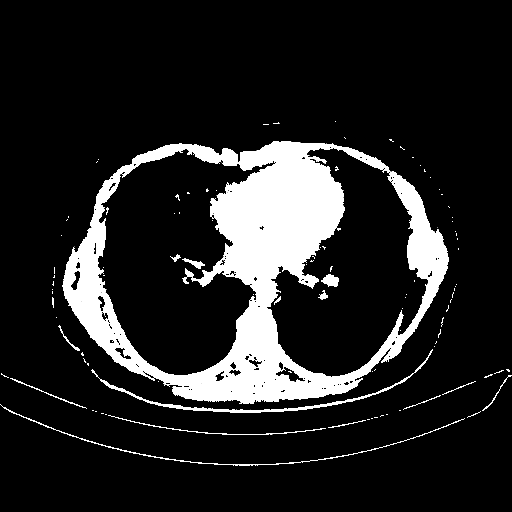

Image Grid

4Γ—3 grid: Rows show different image types (Original NATIVE, Reconstructed NATIVE, Original VENOUS, Generated VENOUS), Columns show windowing techniques (No Window, Lung Window, Mediastinum Window)

Reconstructed NATIVE CT scan (cycle consistency)

Lung window (WL -600, WW 1500 β†’ Low βˆ’1350, High +150)

Actual HU range: [-1350.0, 150.0]

Original VENOUS CT scan

Generated VENOUS CT scan (A→B translation)